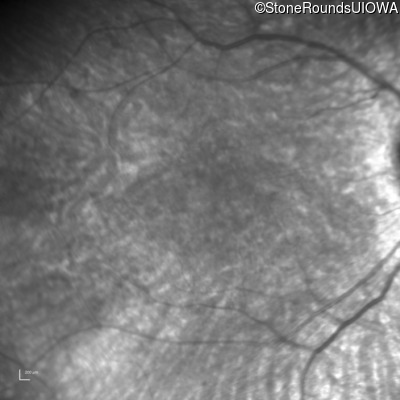

Infrared Fundus Photograph - Right - 20/80 -1

Exemplar